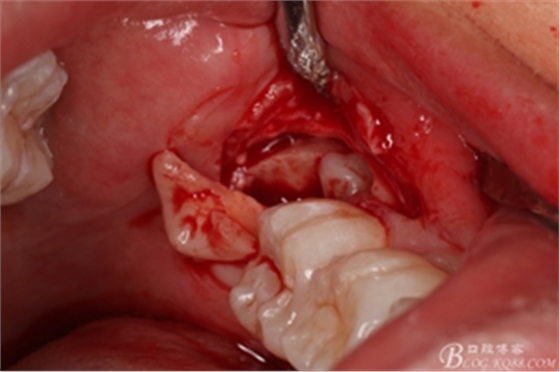

圖13. 分開的38牙冠和牙根

圖14. 分別取出38分開的牙冠